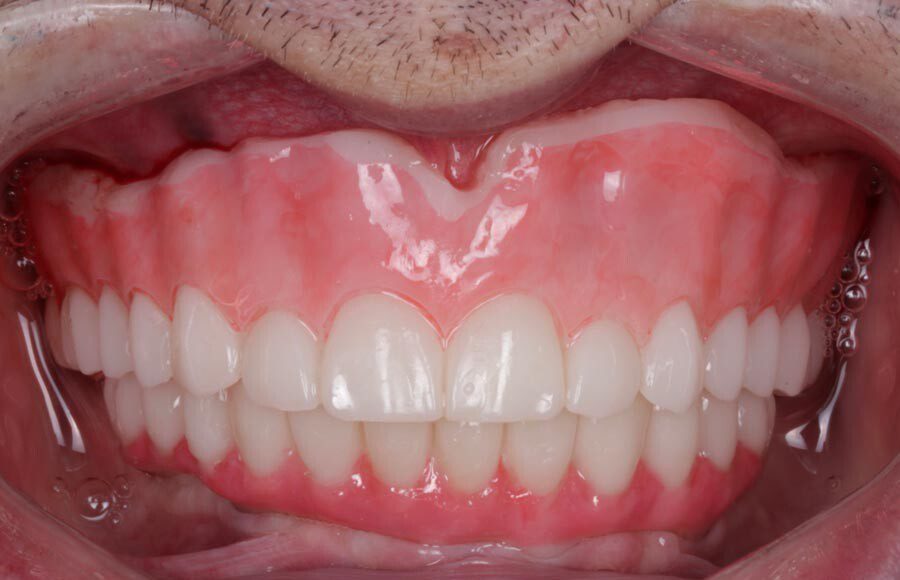

Smile GalleryImplant RestorationsImplant Dentures Post-op smiling 1 of 32 Pre-op close up smiling Pre-op lips retracted smiling Pre-op panoramic x-ray Implants in upper jaw (occlusal view) Implants in lower jaw (occlusal view) Panoramic x-ray of implants First set of try-ins – upper denture First set of try-ins – lower fixed provisional Delivered try-ins (lips retracted) Close adaptation to gums and appropriate emergence profile of lower fixed provisional Gum tissues have been molded by a convex provisional Delivered try-ins Second set of try-ins (lips retracted) Close adaptation to gums and appropriate emergence profile of second set of lower fixed provisional Delivered second try-ins Definitive restorations on casts (frontal view) Definitive restorations on cast (right side) Definitive restorations on cast (left side) Definitive upper overdenture (occlusal view) Definitive lower fixed titanium-acrylic hybrid restoration (occlusal view) Definitive lower fixed titanium-acrylic hybrid restoration (frontal view) Definitive lower fixed titanium-acrylic hybrid restoration (tissue side view) Healthy molded gum tissues on lower prior to delivery of lower fixed hybrid restoration Healthy gum tissues on upper prior to delivery of upper overdenture Definitive restorations (frontal, lips retracted) Definitive lower restoration (frontal) Definitive restorations (right side) Definitive restorations (left side) Definitive lower restoration (occlusal view) Definitive upper restoration (occlusal view) Post-op panoramic x-ray Post-op smiling